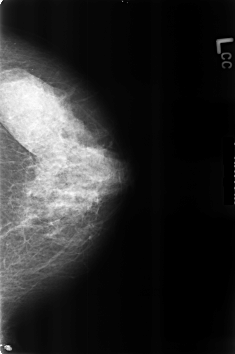

B_3226_1.LEFT_CC

LEFT_CC LINES 4600 PIXELS_PER_LINE 3048 BITS_PER_PIXEL 12 RESOLUTION 50 NON_OVERLAY